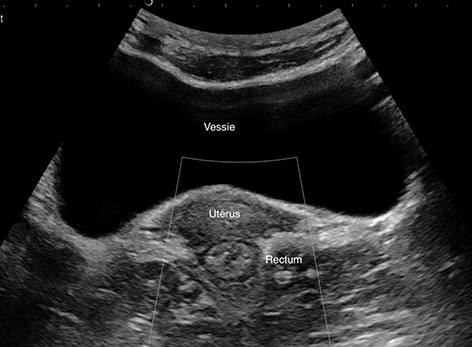

Situé en arrière de la vessie (on le voit mieux vessie semi pleine)

Ici rectum, femme en coupe transversale en arrière de l'utérus en basse fréquence